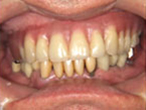

Case.03 オールオン4+即日完了治療症例

初診時

上顎は歯がすべてない状態で総義歯、下顎は大臼歯部に歯が無く小臼歯部に2本づつインプラントが埋入された状態で来院されました。上顎のインプラント治療を希望されていましたが、パノラマレントゲンでは上顎の骨の状態を診断することは不可能でした。そのためCT撮影を行いコンピュータ・シミュレーションで治療計画を立てることにしました。

レントゲン

正面

上顎